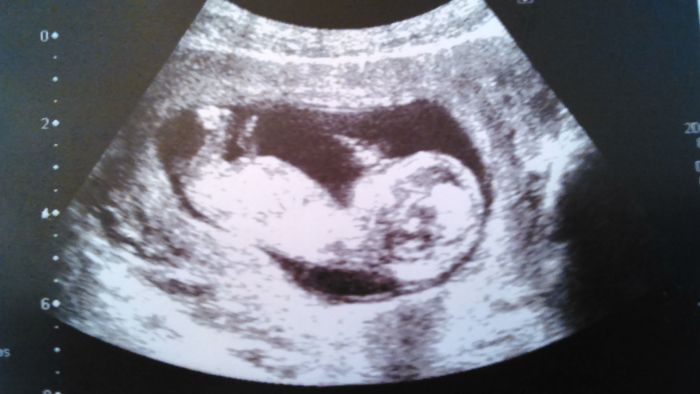

Ahoj holky, tak screening máme za sebou a dopadl dobře.:-) Doktor říkal, že čekáme holčičku, ale budoucí tatinek tvrdí, že to bude kluk, tak kdo bude mít nakonec pravdu...? :-))) Bylo hezké jak koukal na obrazovku a ani nedutal.

Ahoj holky, ufff, tak taky mae screening za sebou - Broucek je podle utz uplne v poradku, od minuleho tydne zase o kus vyrostl, uz jsme 13+2, huraaaa, 1.trimestr je za nama :). Partner byl nadseny, byl to moc pekny zazitek....Vysledky krevnich testu ale budou az za 14dnu, tak snad budou take ok...Pekny vecer vsem;)!

[757669]Ahoj Zuzko, nam co to bude nerekli, ale doktorka mi ukazala Brouckuv zadecek se zvednutyma nozickama a pry at si domyslime, co to bude.....shodli jsme se s partnerem, ze na holcicku to uplne nevypadalo

Mě by zajímalo, podle čeho to poznal... Mimi mělo nožičky křížem a odmitalo se natočit tak, jak potřeboval. :-) Jsem zvědavá, jestli to na dalších utz potvrdí. Já jsem šťastná ať je to kluk nebo holčička. :-)))

Ahoj, tak screening už mám za sebou a dopadl dobře, odpovídáme 12+4, mudr.nám řekla, že to zatím vypadá na holčičku.Takhle brzo vím pohlaví poprvé, myslíte, že tomu už můžu věřit?